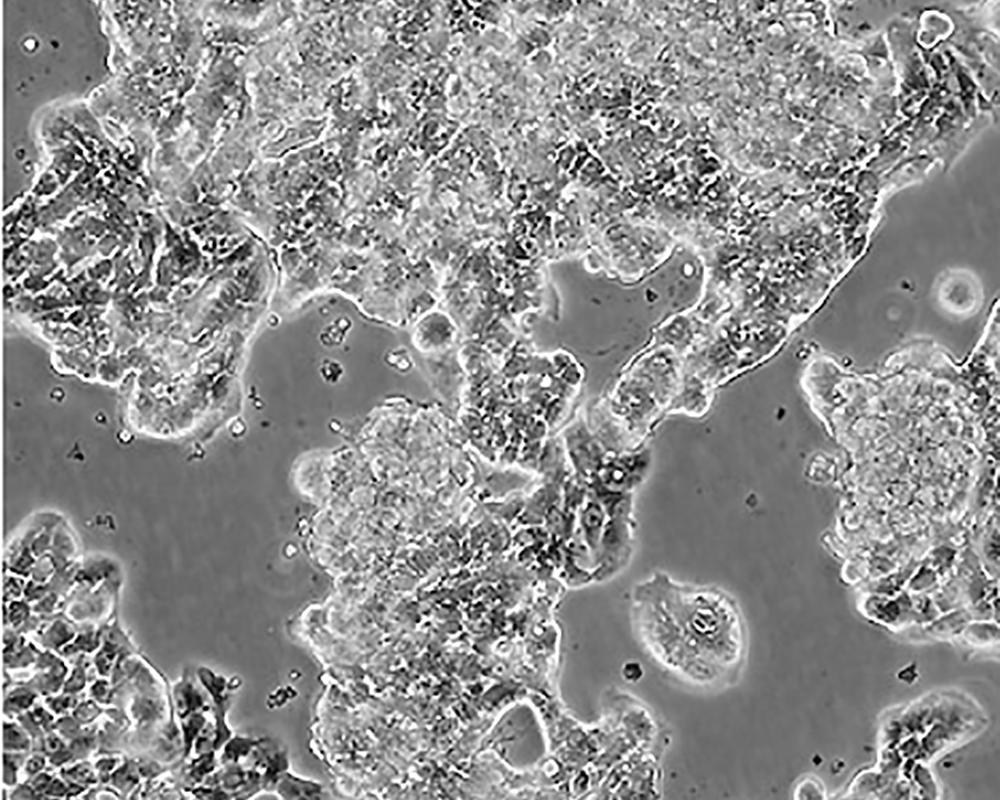

產品名稱 ZR-75-1 [ZR751]

中文名稱 人乳腺癌細胞

組織來源 浸潤性導管癌;腹水轉移;女性

生長特性 adherent

形態特征 epithelial

細胞描述 該細胞產生高水平的黏液素MUC-1 mRNA,低水平的MUC-2 mRNA,但不表達MUC-3基因;表達雌激素受體。